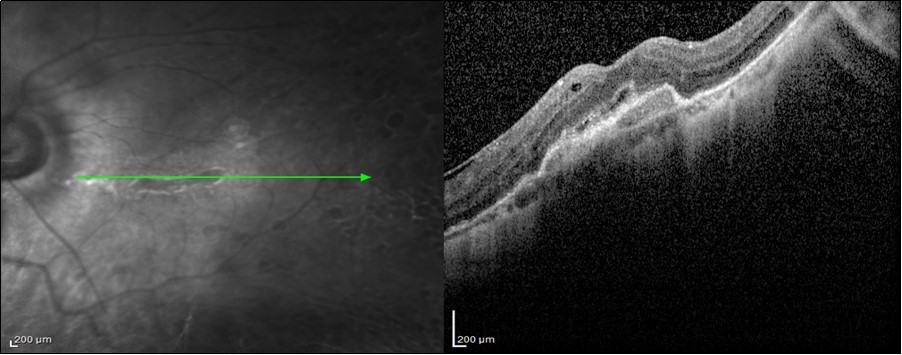

Post-SOR SD-OCT macular findings were Photorecepter layer disruption 6 (50%), Epiretinal membrane 4 eyes (33.3%) Figure 1, macular hole 1 eye (8.1) and choroidal neovasculrization on 1 eye (8.3%) Figure 2 with significant correlation with final post-SOR BCVA p value 0.048 Table 3.

Figure 1.4 years Post-SOR SD-OCT image of a 42-year-old patient with BCVA 6/12 after anatomical repair of a macula-on GRT with PPV + SOI with preoperative BCVA 6/18. We can, notice the presence ERM and CME.

Figure 2.3 years Post-SOR SD-OCT image of a 44-year-old patient with BCVA 6/36 after anatomical repair of a macula-on GRT with encilrclage PPV + SOI with preoperative BCVA 6/6. We can notice the presence of SRNVM, IS/OS (ellipsoid zone) disruption, and RPE changes.